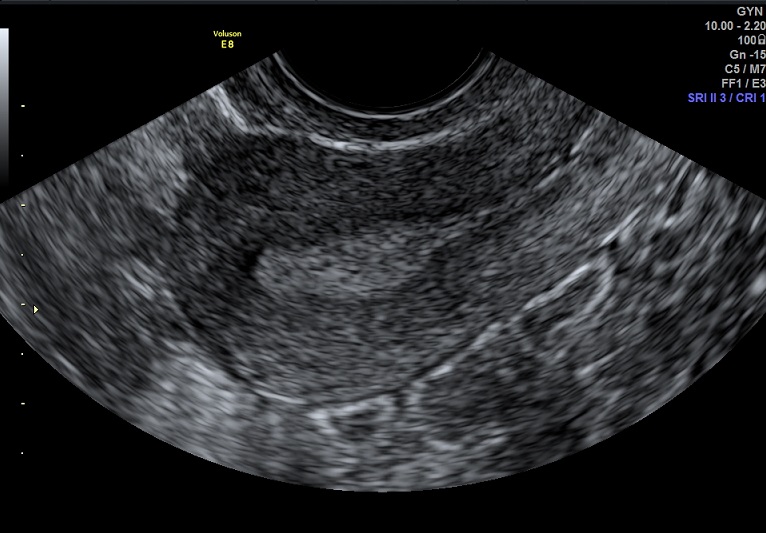

女性,24岁,原发性不孕1年余。

2015-3-10 月经第19天检查

内膜厚0.7cm

内膜血流:2级

内膜波动可见

左卵巢黄体 右卵巢囊性结构